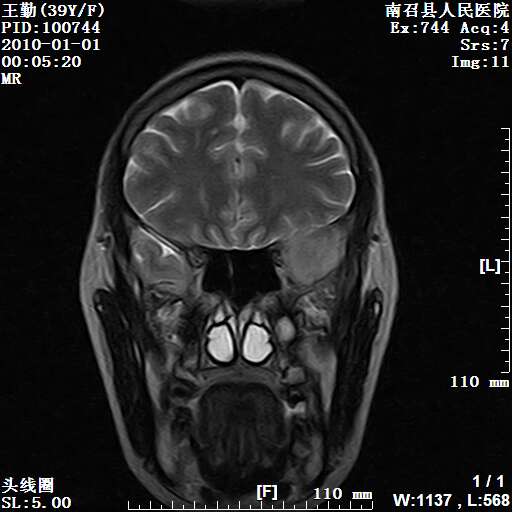

以下是引用随光逐影在2010-1-22 9:03:00的发言:[br]考虑左侧中颅窝(蝶骨翼区)脑膜瘤侵犯蝶骨翼并突入左侧眼眶。

以下是引用水过无痕在2010-1-22 14:55:00的发言:[br]一、定位:颅外占位;二、定性:恶性可能性大;三、组织来源:来源于左侧眼外直肌或其他部位;考虑为:横纹肌肉瘤>转移瘤>脑膜瘤.